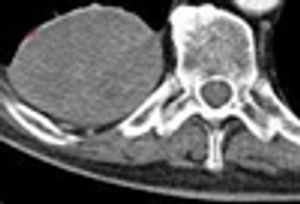

A 76-year-old man presented with left-sided chest pain, after a fall. He had tenderness along the left 8th rib and left basal rales. CXR showed non-displaced fractures of the 7th and 8th ribs with a small effusion and a right postero-basal rounded opacity.